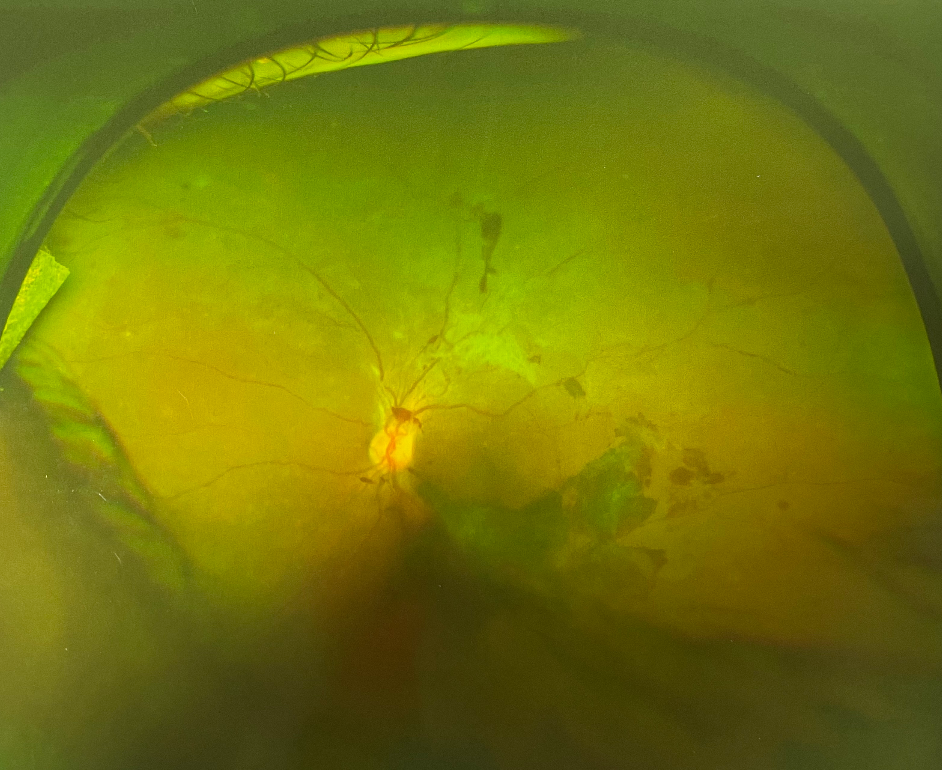

眼底出血是眼底視網(wǎng)膜血管的病變引起的。正常情況下,血液在人體的血管內(nèi)流動(dòng),不會(huì)溢出,但如果身體出了問(wèn)題,無(wú)論是眼睛局部的問(wèn)題還是全身的病變,在眼睛血管里流動(dòng)的血液就會(huì)溢出來(lái),溢在視網(wǎng)膜上,這就形成了眼底出血。那么眼底出血的癥狀有哪些呢?

眼底出血的癥狀1、突然眼前一片漆黑,僅見手動(dòng)或僅有光感。

眼底出血的癥狀2、驟然間眼前如有圓的黑影遮住,不隨眼轉(zhuǎn)動(dòng)而漂浮,正中方向注視物體完全不見,兩旁物體則模糊可見。

眼底出血的癥狀3、突然眼內(nèi)有如線條狀黑影向某一方向直射,進(jìn)展迅速,且逐漸加多,遮住眼前,視物一片模糊,無(wú)法分辨。

眼底出血的癥狀4、驟然眼前出現(xiàn)紅光閃閃,逐漸加多,以致紅光滿目,視物不明。

眼底出血的癥狀5、發(fā)病先兆,多數(shù)有眼脹,眼珠跳動(dòng)等感覺(jué)。

如果出現(xiàn)上述眼底出血的癥狀,急!需到醫(yī)院眼科進(jìn)行詳細(xì)的眼底檢查,及時(shí)發(fā)現(xiàn)病因及時(shí)治療,治療的時(shí)機(jī)直接關(guān)系著視力的恢復(fù)情況。

由于眼底出血的原因及部位不同,預(yù)后及對(duì)患者視力的影響也不一樣,依照出血量的多少,出血部位不同而產(chǎn)生不同的癥狀。如出血量少,位于視乳頭及視網(wǎng)膜周邊部,可以沒(méi)有明顯眼底出血的癥狀,如出血量多,患者感到眼前有黑影浮動(dòng),視線被部分或完全遮擋,僅剩光感的視力。如出血位于視網(wǎng)膜中心(黃斑區(qū))患者中心視力喪失,即中心區(qū)視物不清有暗影遮擋,周邊尚有部分視力。